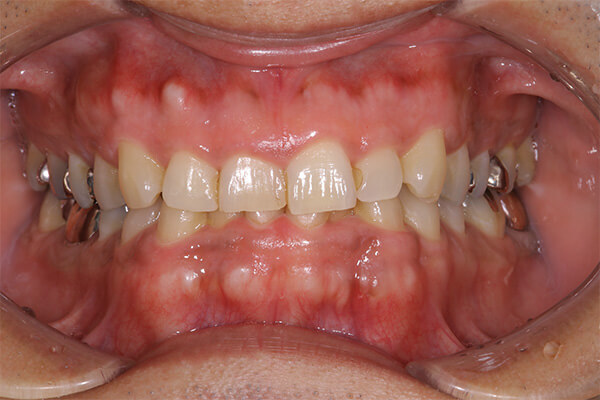

セラミックインレーの装着時には写真のようにラバーダムというゴムのシートを使うことにより接着力が増します。